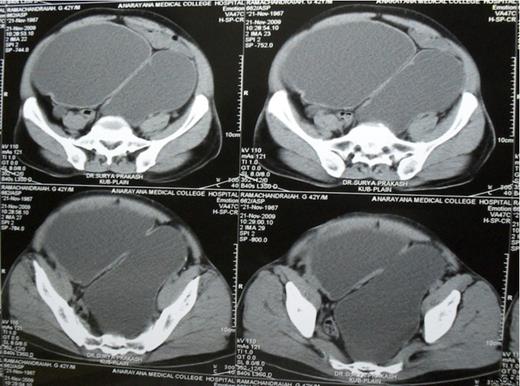

A 42 year old adult presented with poor urinary stream and lower abdominal pain over the last year. On examination he had a grossly distended bladder extending from the hypogastrium up to the right hypochondrium. External genitalia was normal. An ultrasound abdomen revealed a large bladder diverticulum in the left posterolateral aspect of bladder, mild right sided hydronephrosis with a right renal calculus and severe left hydroureteronephrosis with a thinned out cortex. Voiding cystourethrogram (VCUG) showed large bladder diverticulum with no evidence of reflux and normal posterior urethra. Intravenous urogram (IVU) and DTPA renogram revealed a non-functioning left kidney. A CT-KUB confirmed mild right sided hydronephrosis with a 1cm renal calculus, severe left sided hydroureteronephrosis and a large bladder diverticulum (Fig. 1).

Plain CT scan of abdomen and pelvis showing large bladder diverticulum posterior to the bladder